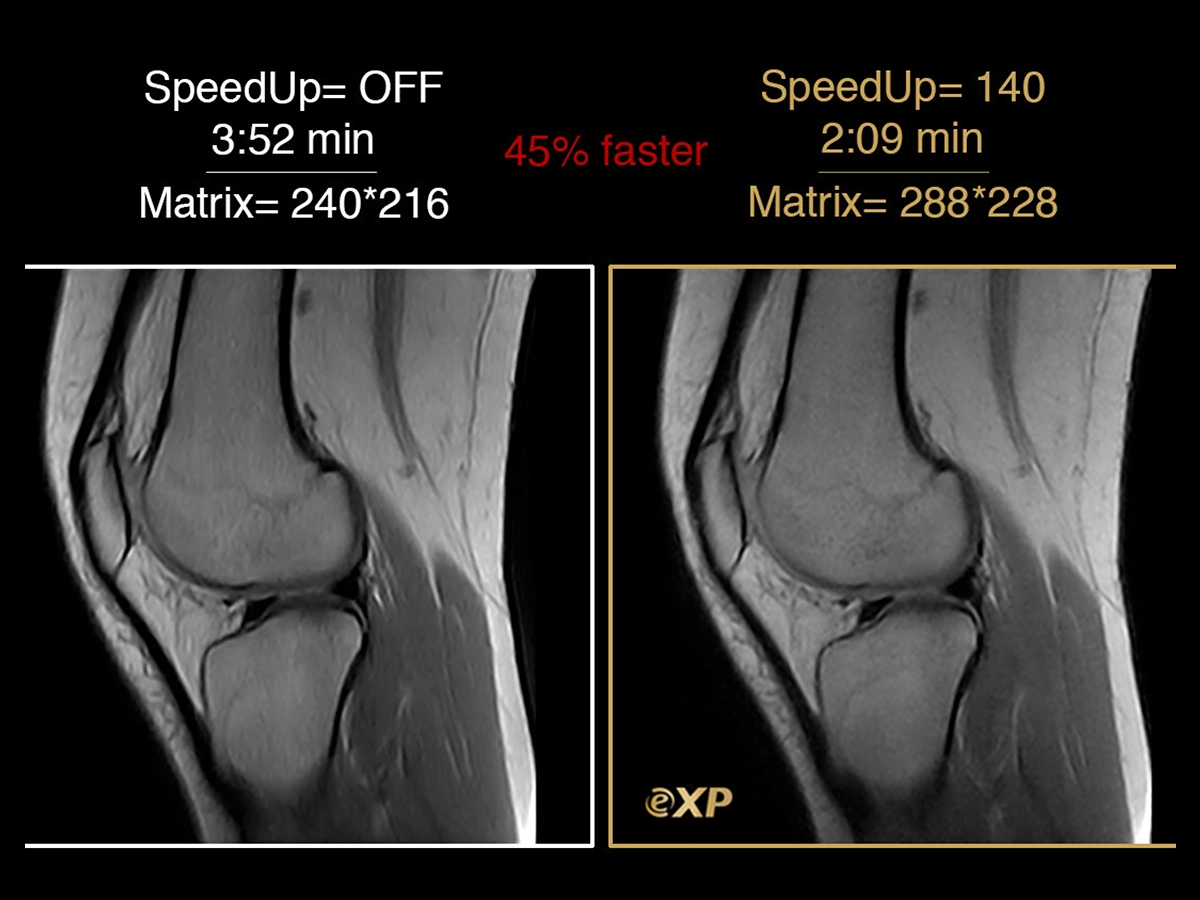

SpeedUp

The Esaote Compressed Sensing reconstruction.

- Is the accelerating MR data acquisition developed by Esaote, based on semi-random, incomplete sampling of k-space.

- Esaote patented technology developed by our R&D department.

- Available on Esaote MRI since 2015. First manufacturer to introduce it to the market.

SpeedUp: How does it work and what does it do?

Faster exams:

SpeedUp allows sensible reduction of the scan time through a in-choerent sparse sampling of the K Space.Reduces artifacts and noise:

SpeedUp technique through an iterative nonlinear regression algorithm permits to reduce image artifacts and background noise improving overall image quality.